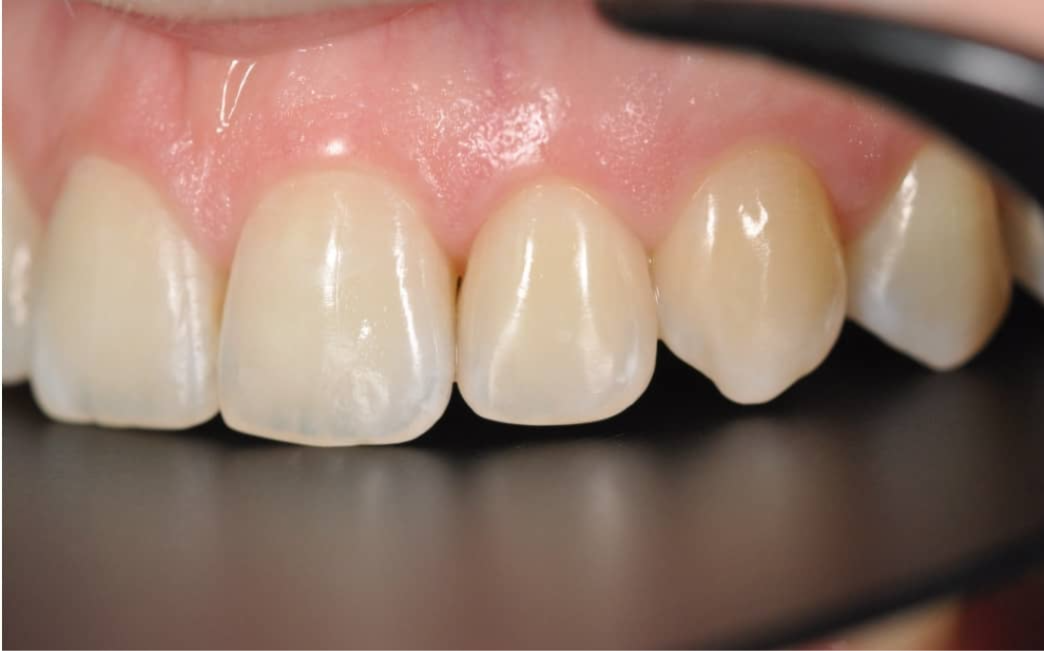

Этап №4

Финишная реставрация

После снятия брекет-системы стоматолог-терапевт провела художественную реставрацию формы боковых резцов, добившись идеальной гармонии и естественности улыбки.

Эстетика

Исправлен прямой прикус, восстановлена форма резцов, а улыбка стала не только красивой, но и здоровой с точки зрения биомеханики.